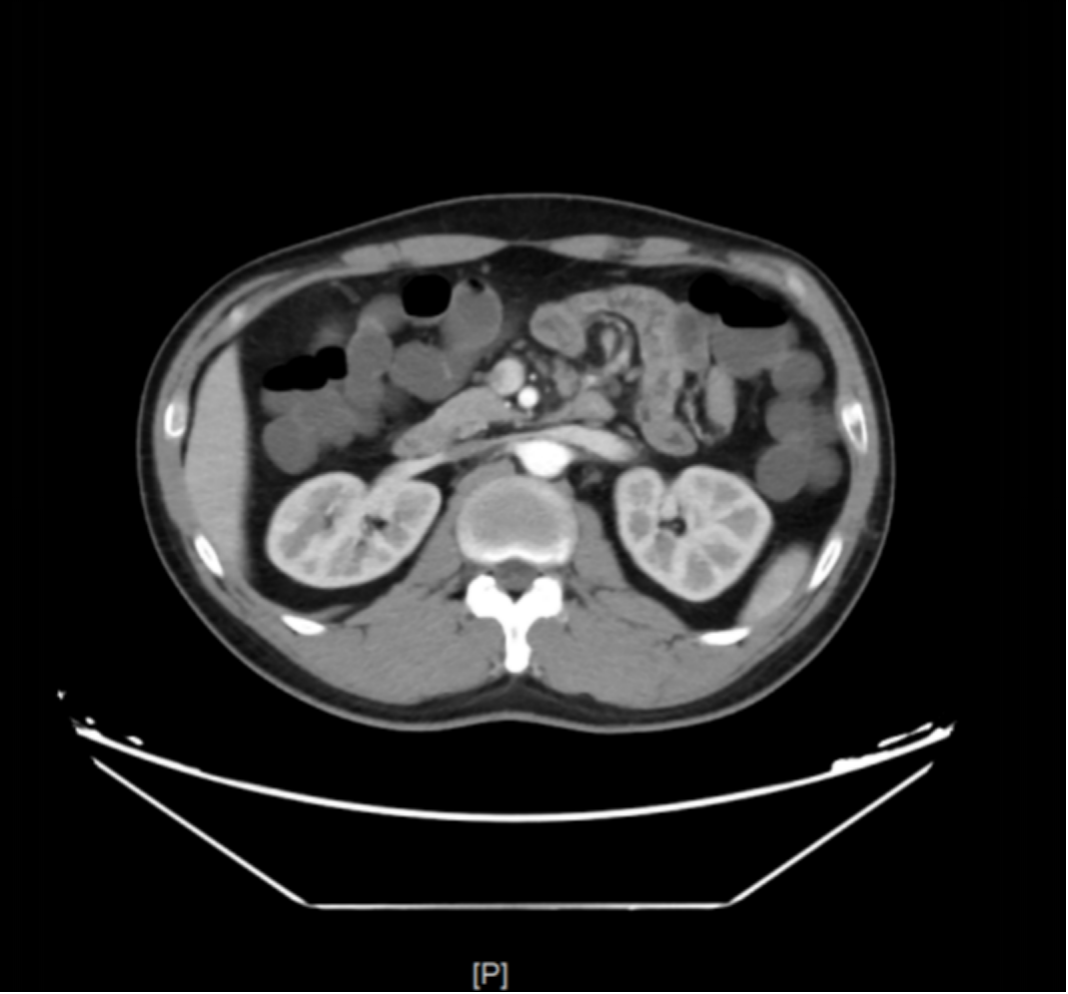

麻醉肠镜(图4

回肠末段未见异常;结直肠多发息肉(4枚CFP);内痔。

图4 肠镜示结肠息肉

肠镜病理

1、(回末黏膜活检组织)黏膜局灶性炎,伴淋巴滤泡形成。刚果红(-)。 2、(横结肠黏膜活检组织)符合增生性息肉。刚果红(-)。 3、(直肠黏膜活检组织)增生性息肉。刚果红(-)。